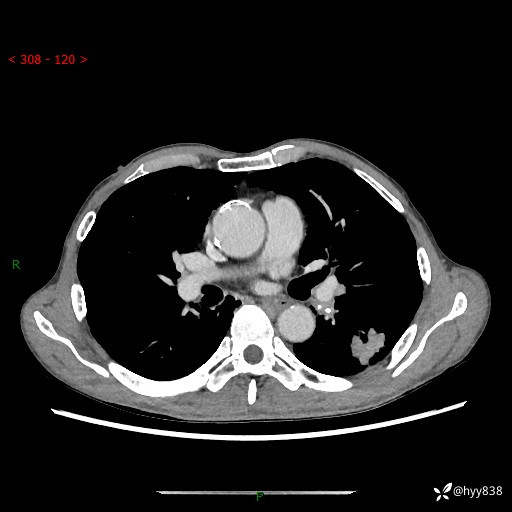

现病史:患者于1月余前无明显诱因出现背部疼痛不适,无明显咳嗽、咳痰、胸闷、咯血、发热等不适,后于2024.5.3至当地市人民医院行胸部CT示:左肺下叶结块,大小约2.2cm*2.6cm,双肺多发小结节,双肺感染性病变,部分纤维增值灶,慢支并双肺局限性肺气肿,肺大泡,纵隔淋巴结增大并部分钙化,冠脉区及大血管壁钙化,双侧胸膜局限性增厚;后口服莫西沙星2周。2024.6.12复查胸部CT示:左肺下叶结块影形态较前饱满,较大截面范围约2.8cm*2.3cm,边缘可见细短毛刺及分叶,性质待查。现患者为求进一步诊治来我院,门诊以“肺占位”收入我科。 起病来,患者精神、食欲、睡眠尚可,大小便正常,体力体重轻微下降。

胸部CT平扫+增强

各期CT值:48hu 100hu 78hu